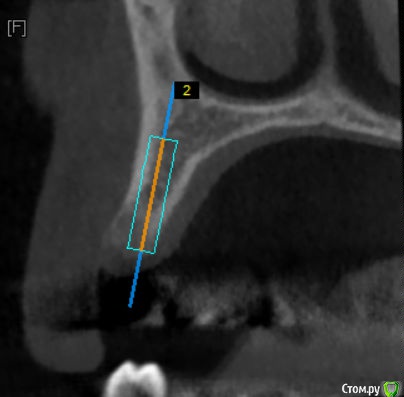

Kazankov.Egor Опубликовано 17 мая, 2018 Поделиться Опубликовано 17 мая, 2018 Господа ветераны, делать нкр или поставить винт 3.3+сст? Бояться ли в данном случае угла (в связи с функцией коронки)? Ссылка на комментарий

Nazim_NV86 Опубликовано 17 мая, 2018 Поделиться Опубликовано 17 мая, 2018 Главное вестибулярно кортикалку не испортить. 3.3-3.5 легко закрутится. Чуть расщепить можно, +1мм будет. Ссылка на комментарий

Evikrol Опубликовано 17 мая, 2018 Поделиться Опубликовано 17 мая, 2018 3,5 на 11,5 или 13 мм и заглубится + сст 3 Ссылка на комментарий

Kazankov.Egor Опубликовано 17 мая, 2018 Автор Поделиться Опубликовано 17 мая, 2018 Главное вестибулярно кортикалку не испортить. 3.3-3.5 легко закрутится. Чуть расщепить можно, +1мм будет.Распилы не делать вертикальные? Просто сделать горизонтальный по вершине гребня и расширить? Как в случае расщепа модифицируется протокол сверления? Планирую BL 3,3#13.Лучший ли выбор для такой ситуации? Ссылка на комментарий

kriokov Опубликовано 17 мая, 2018 Поделиться Опубликовано 17 мая, 2018 Распилы не делать вертикальные? Просто сделать горизонтальный по вершине гребня и расширить? cистема какая болтов? Не надо ничего под 3.3 расщеплять, пилот , остеотом, и вкручивайте. ССТ. 3 Ссылка на комментарий